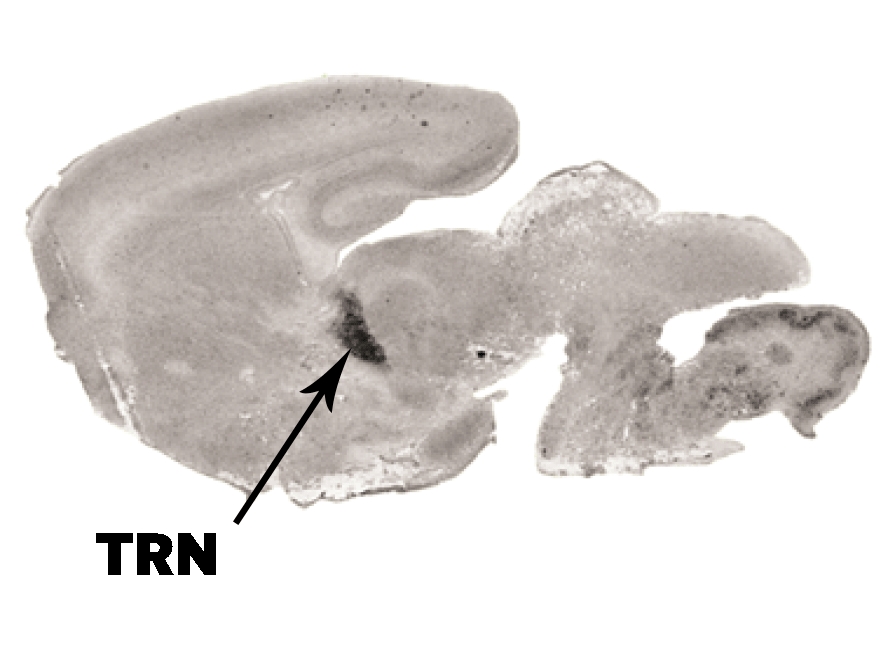

The region of the thalamic reticular nucleus, or TRN, in the mouse brain, where PTCHD1 gene is active Image courtesy of Nature

Back in October, Michael Halassa, a neuroscientist at New York University and a co-author of the new study, published a paper that found that a region of the brain called the thalamic reticular nucleus, or TRN, is responsible for controlling the brain’s ability to multitask. Acting as a task switchboard, the TRN processes sensory stimuli that come in, decides what’s most important, and directs attention to that. But for disorders like ADHD, autism, and schizophrenia, something within the TRN goes awry, making it harder, if not impossible for people with ADHD to focus on a particular task, or for people with autism to socialize, for example.

Halassa and his team, including Guoping Feng from MIT, wanted to know what was going on in the TRN to cause this. Previous studies had found that people born with defects in a gene that is most active in the TRN, called the PTCHD1 gene, struggle with sensory overload, leading to these cognitive conditions.